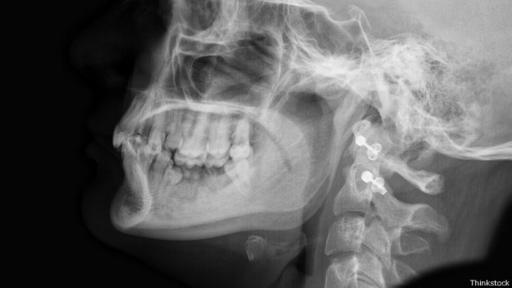

Ni siquiera nuestros parientes extintos contaban con un mentón. (Foto: Thinkstock)

Los otros animales, incluidos chimpancés y simios, tienen una mandíbula que se inclina hacia adentro. Incluso los neandertales, nuestros parientes extintos, carecían de ella.

De hecho, una de las formas en que los científicos pueden diferenciar un cráneo de humano moderno de un neandertal es por el mentón (o su ausencia).